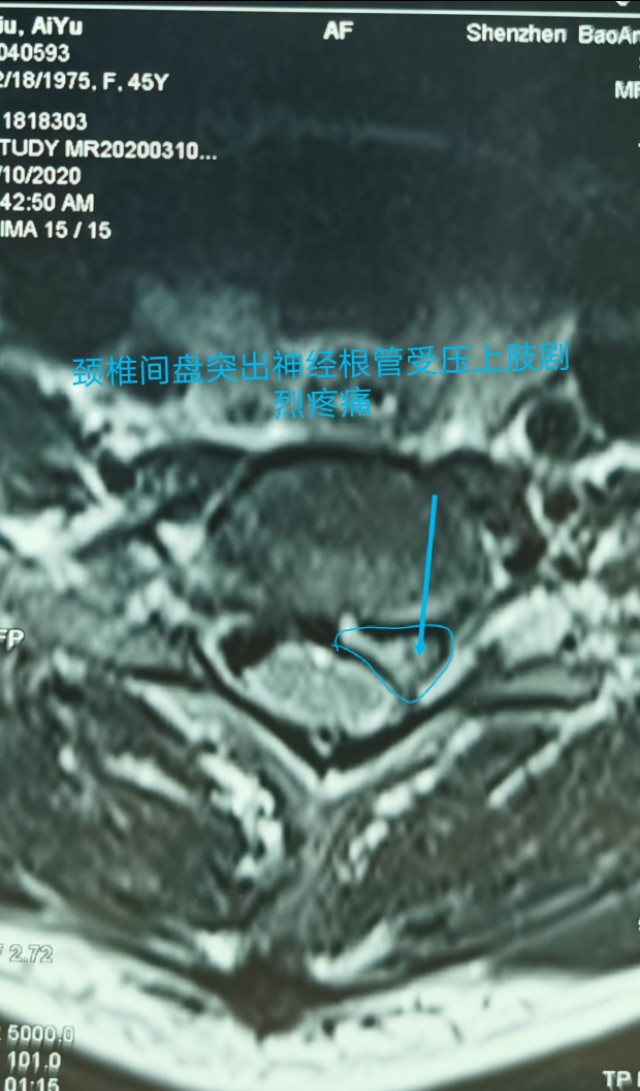

中年人疫情期居家长期卧床及长期看电脑手机,颈椎病复发今天显微镜下微创治疗,颈6-7巨大椎间盘突出.压迫神经根管,伴左上肢剧烈放射痛,显微镜下微创颈椎间盘突出治疗,用时半个小时,近零出血,取出压迫神经4块髓核,切除后纵韧带,减压至脊髓表面,脊髓恢复正常搏动,神经监护神经功能恢复好